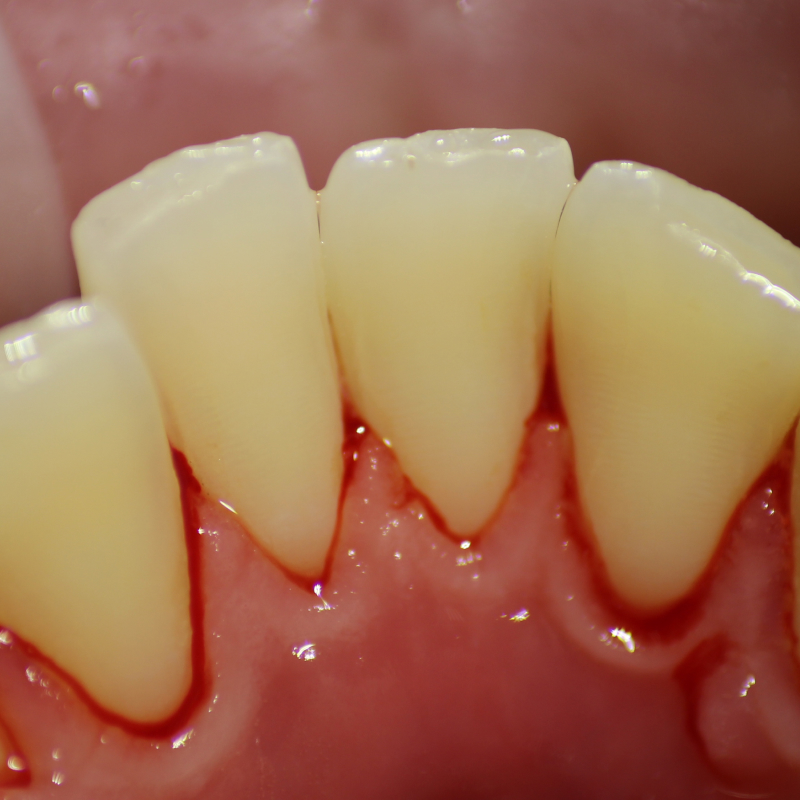

Выполнение профессиональной гигиены для снятия минерализованных зубных отложений и пигментированного налётаСмотреть работуСрок лечения:1 часСумма лечения:3 850 руб.

Процедура профессиональной гигиены для снятия минерализованных зубных отложений и пигментированного налётаСмотреть работуСрок лечения:40 мин.Сумма лечения:3 850 руб.

Процедура профессиональной гигиены для снятия минерализованных зубных отложений и пигментированного налёта.Смотреть работуСрок лечения:45 мин.Сумма лечения:3 850 руб.

Удаление десневых и зубных отложений с помощью УЗ-аппаратаСмотреть работуСрок лечения:60 мин.Сумма лечения:3 880 руб.